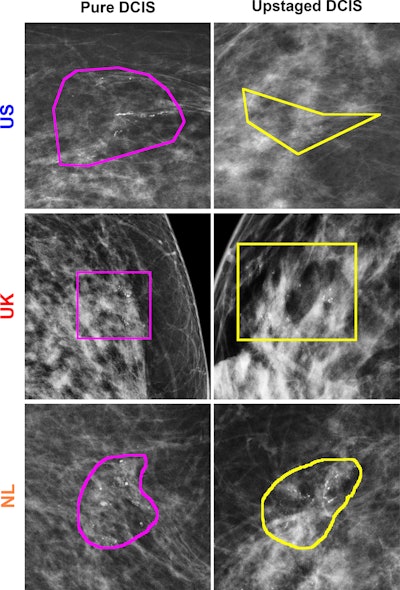

Examples of correctly predicted lesions among three countries using the model trained on images from the U.S. dataset. Lesion annotations were provided by the study radiologists at each site. The regions of interest indicate lesion annotations.Examples of correctly predicted lesions among three countries using the model trained on images from the U.S. dataset. Lesion annotations were provided by the study radiologists at each site. The regions of interest indicate lesion annotations.RSNA

Hou and colleagues evaluated the performance of radiomics models tested in three national datasets from the U.S., the U.K., and the Netherlands. The study included data collected between 2000 and 2021, and all women were diagnosed with DCIS at core-needle biopsy.